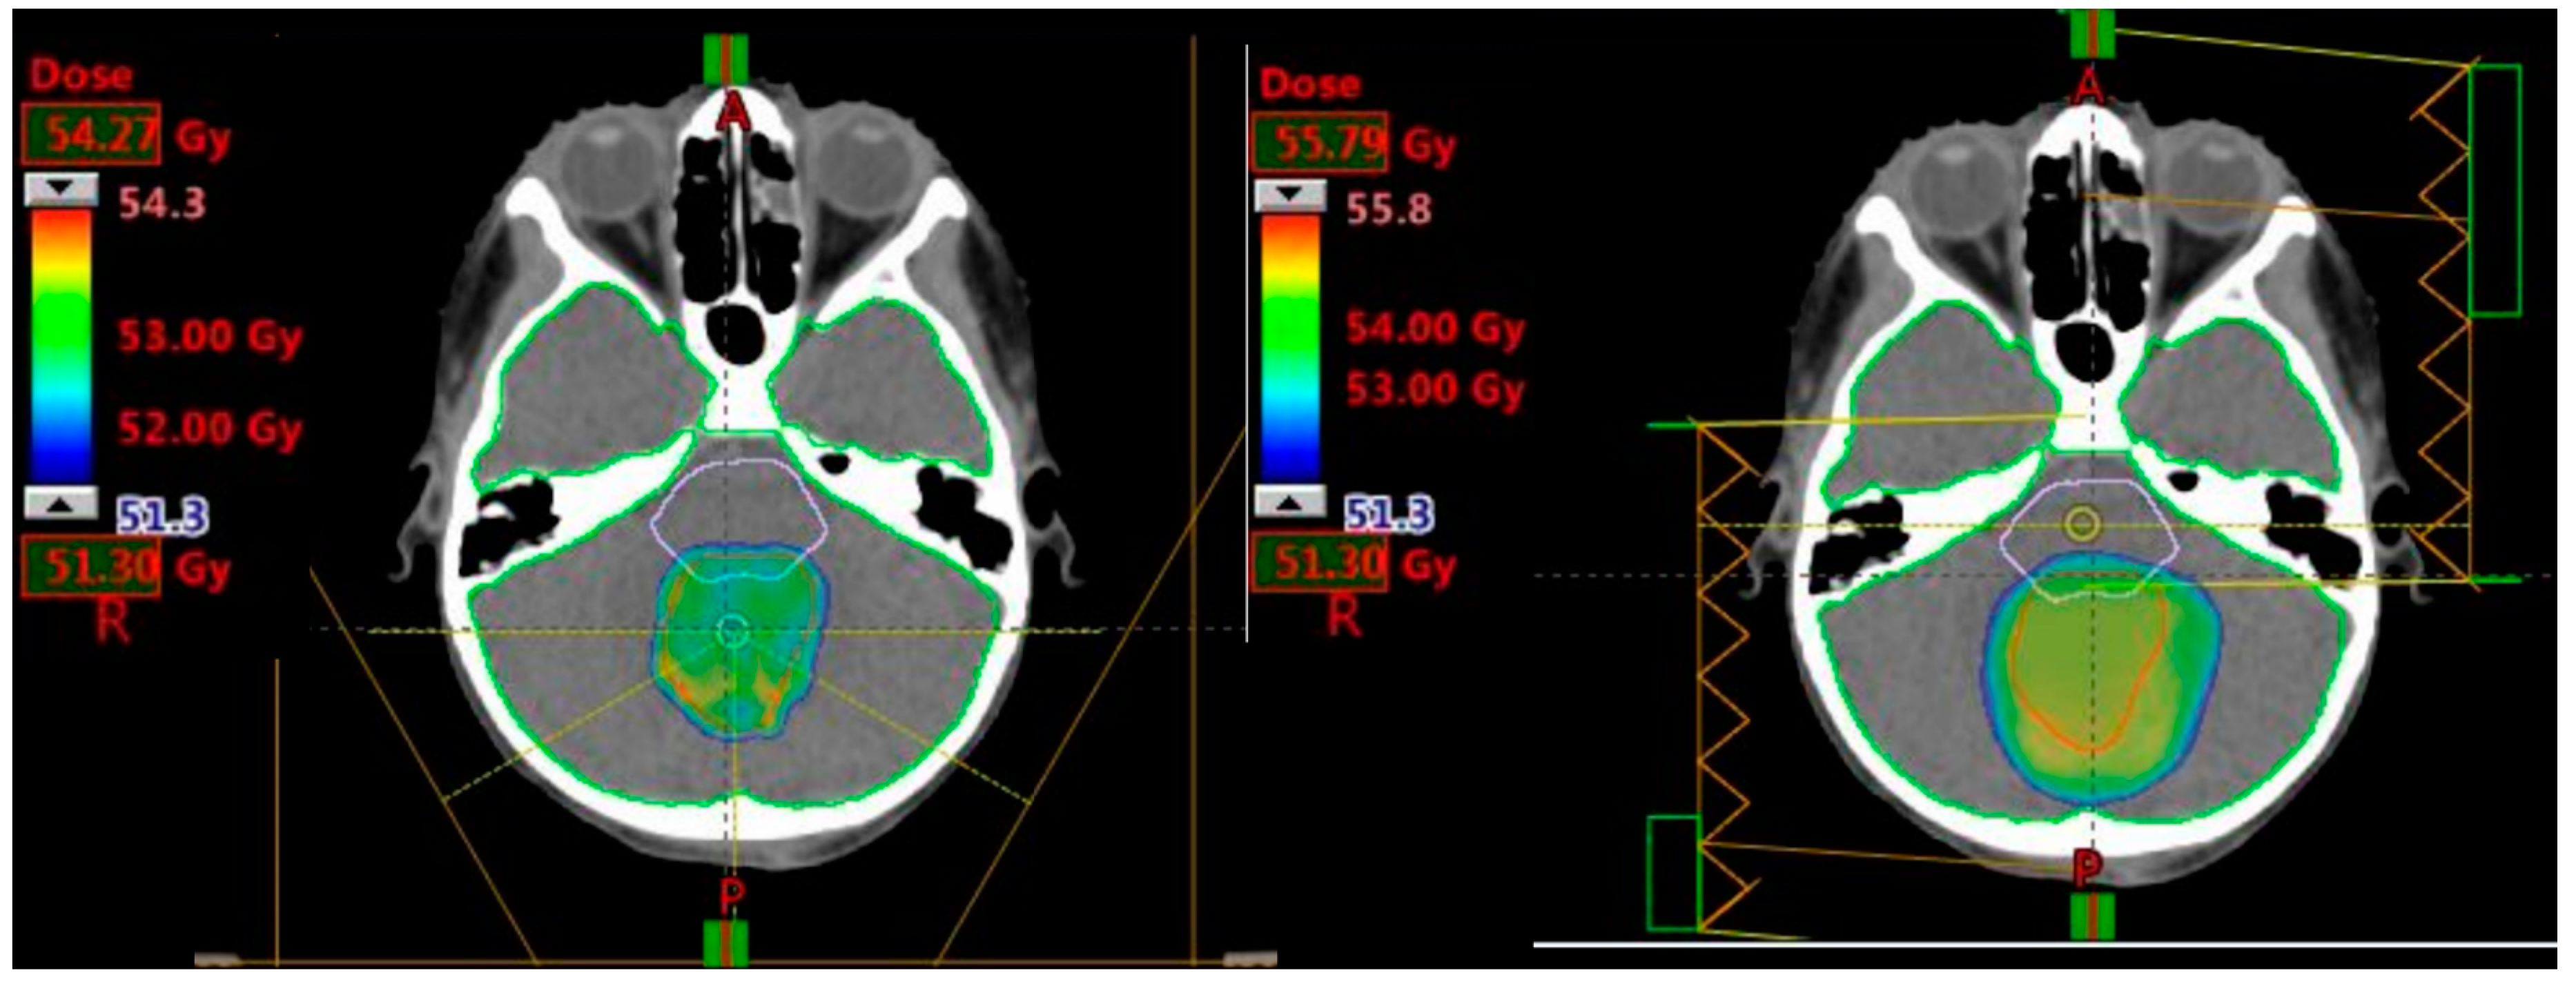

2.2.1. Prescribed Dose and Beam Arrangement for Intensity-Modulated Proton Therapy (IMPT)

2.2.2. Prescribed Dose and Beam Arrangement for Intensity-Modulated Photon Therapy (IMRT)